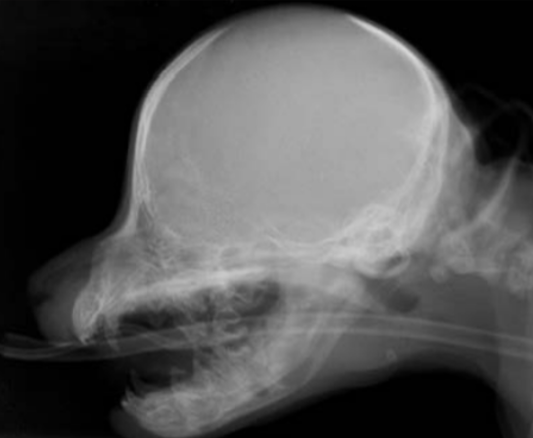

18

Q

identify pathology

A

left zygomatic arch neoplasia in left image

asterisk marks soft tissue neoplasia in left side image. note the difference in density of that space.